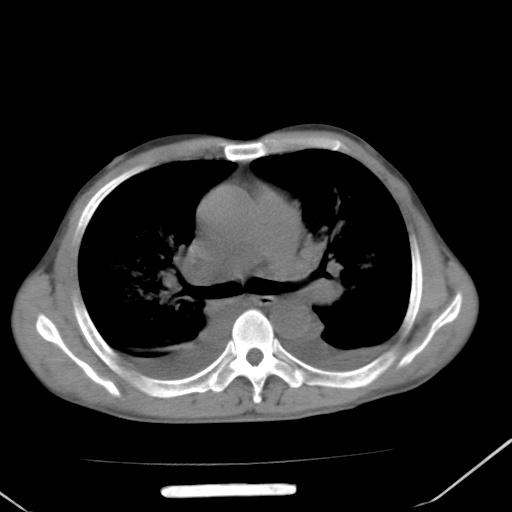

男、42岁、咯血3天。既往有甲亢、贫血、血尿蛋白尿史多年。血象:wbc:6.   中性粒:70.6%。

左心房增大,考虑心衰,肺水肿。

双肺野广泛对称性磨玻璃影、实变影,以肺门为中心,主要分布于内中带,符合典型肺泡性肺水肿;伴双侧胸腔少量游离积液。结合患者既往病史且咯血就诊,支持多因素(尿毒症等)所致之肺水肿、肺出血、胸水;影像表现暂不考虑心源性水肿,且症状也不太符。需密切随诊结合临床治疗等进一步明确。

心影增大密度略低,双肺磨玻璃样高密度影及双侧胸腔积液,考虑心功能不全继发双肺肺水肿及双侧胸腔积液。心影密度略低,考虑贫血所致。

双肺野对称性磨玻璃影,分布于内中带,双侧胸水,患者有咯血。